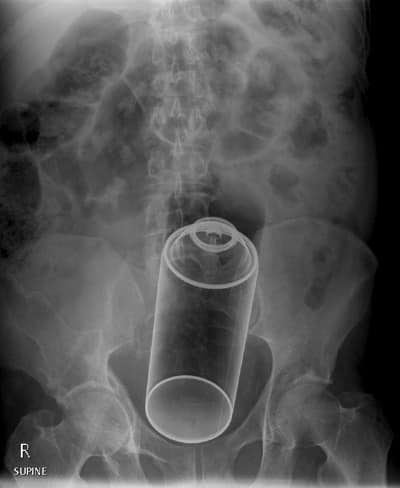

6. Un aérosol

Les aérosols sont connus pour faire un trou dans la couche de zone mais aussi autre part…

aerosol

(source photo : ebaumsworld)